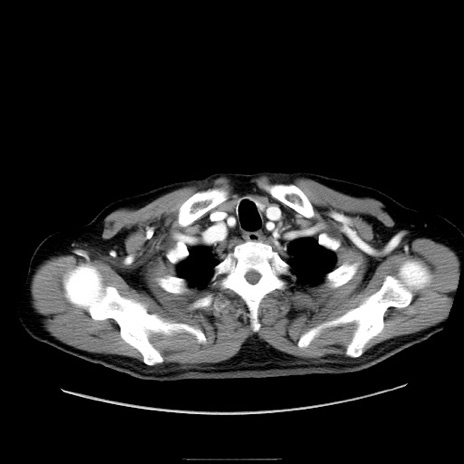

症例30(横断像)

【症例】80歳代男性

【主訴】臍周囲痛

【現病歴】約6時間前から臍下部痛が出現。次第に腹部膨隆・背部痛も生じてきたため来院。背部痛の場所は変化しない。

【身体所見】意識清明、BT 36.3℃、BP  131/87mmHg、P 87bpm、SpO2 100%(RA)、臍周囲自発痛・圧痛あり、反跳痛なし、自発痛部位に一致して板状硬あり、腹部膨隆、腸雑音減弱、CVA tenderness両側陰性。